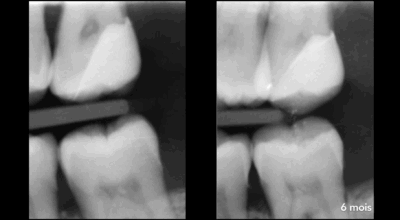

Clinical case of tooth 17 (upper right second molar)

Indirect pulp capping: 96.4% success rate